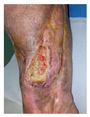

5.4. Clinical Case Series: 3D Dr. Invivo Bioprinter Experience

5.4.1. Overview

The proposed case series evaluated the clinical efficacy of the 3D Dr. INVIVO Bioprinter, an extrusion-based bioprinting system, in treating refractory chronic wounds. This study provides important real evidence for the clinical translation of 3D bioprinting technology in wound care.

5.4.2. Patient Population and Study Design

Four patients (2 male, 2 female; age range 62-78 years, mean age 70 years) with chronic wounds failing to heal after more than 4 years of both conservative and surgical treatment were enrolled. All patients presented with:

Wound duration: >4 years of failed treatment

Comorbidities: Stage 2 arterial hypertension (well-controlled) in all patients (100%); diabetes mellitus type 2 (well-controlled) in one patient (25%)

Infection status: Microbiological examination confirmed absence of active infection in all cases

Previous treatments: Multiple debridements, advanced wound dressings, negative pressure wound therapy, and failed surgical interventions including skin grafting and local flap reconstruction

Inclusion Criteria: - Documented failure to heal after ≥4 years of treatment; Failed conservative and surgical management; Medical optimization of comorbidities; Patient consent for novel therapeutic approach.

3. Wound Bed Preparation and Debridement, Photo of the Wound

4. Liposuction, Preparation and Application of 3d Bioprinted Material (Figure 4)

5.4.4. Clinical Outcomes

Overall Healing Success: Complete epithelialization at 11 weeks: 3/4 patients (75%) Incomplete epithelialization requiring intervention: 1/4 patients (25%)